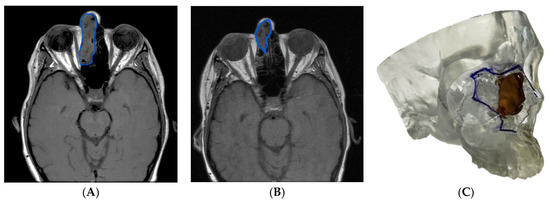

3.1.1. Case 1: Application of a 3D Model in Sinonasal and Skull Base Tumor Excision/Ablation